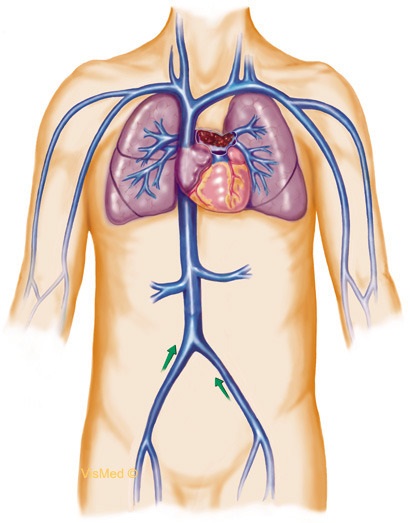

Ha hanyagság vagy gondatlanság az orvosi személyzet intravénás rendszert vagy fecskendő fordult a levegőben, ez veszélyezteti a szélsőséges következményeket és a veszély, hogy az emberi élet! Légbuborék (orvosi kifejezés - embólia) együtt mozog a véráramlás az artériákban első, onnan jut a kisebb ereket, és végül eléri a hajszálerek. Légembóliát blokkok az arteriolák és leállítja a vér áramlását, hogy egy bizonyos része a test, ami egy éles oxigénhiányos. De a legveszélyesebb, amikor ez a légbuborék blokkolja a tüdő, koronária (szív) artéria vagy az agy - halálhoz vezet. Az egyik barátom meghalt, amit maga tett intravénás injekció, így a levegő véletlenül a fecskendőben (

Belépő levegő artéria átfedi véráramlás, hogy megy a szív vagy az agy. Úgy hívják, hogy embólia. Amikor a szív embólia emberekben előfordulhat szívroham, és az agyi embólia - a stroke.

Ha megad egy fecskendő vénába. ez lehet egy légembóliát megjelenése miatt a levegő buborékok az érrendszerben. A levegő bevezetése a vénába rendre vénás embólia fordul elő. lehet életveszélyes az az oka, hogy képes blokkolni a pulmonális véráramlást. De ez természetesen függ a levegő mennyiségét. Úgy tartják, hogy rendkívül veszélyes az emberre, mint mennyiségű levegőt a szellemben, mint 8-10 ml, és így tovább.